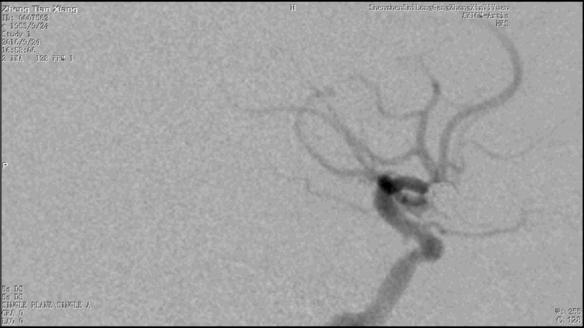

今天为大家分享的是“强生医疗CNV-神经介入专栏”第二十五期,由南方医科大学第三附属医院神经外科主任黄理金教授带来的“Enterprise支架辅助栓塞动脉瘤的优势”精彩讲课视频及PPT,欢迎观看。文章仅代表作者个人观点,如有不同见解,欢迎同道斧正!